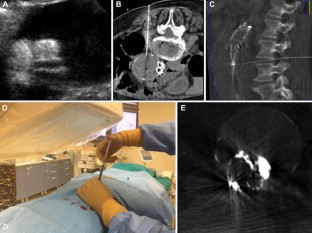

Fig. 1